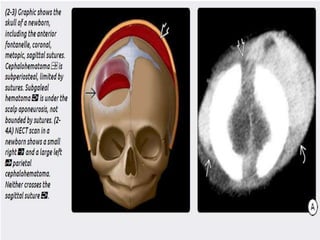

2) Hematoma- cephalohematoma and subgaleal

hematoma. The latter is more severe n can

cause hypovolemia and hypotension.

 Scalp injury– 1) laceration-Focal discontinuity, soft tissue swelling, and subcutaneous air are commonly identified in scalp laceration. Wood fragments are often hypodense, whereas leaded glass, gravel, and metallic shards are variably hyperdense. 2) Hematoma- cephalohematoma and subgaleal hematoma. The latter is more severe n can cause hypovolemia and hypotension.